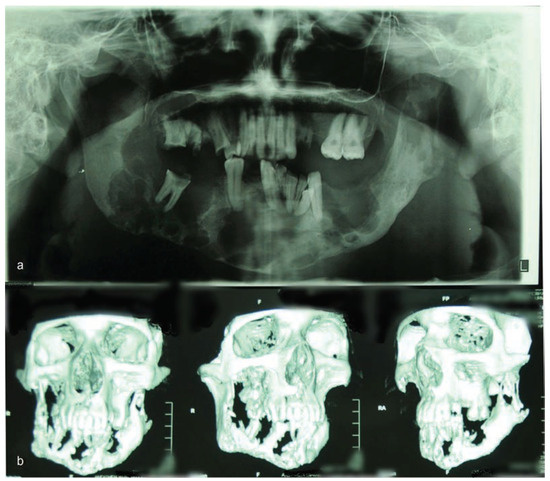

:Case Presentation